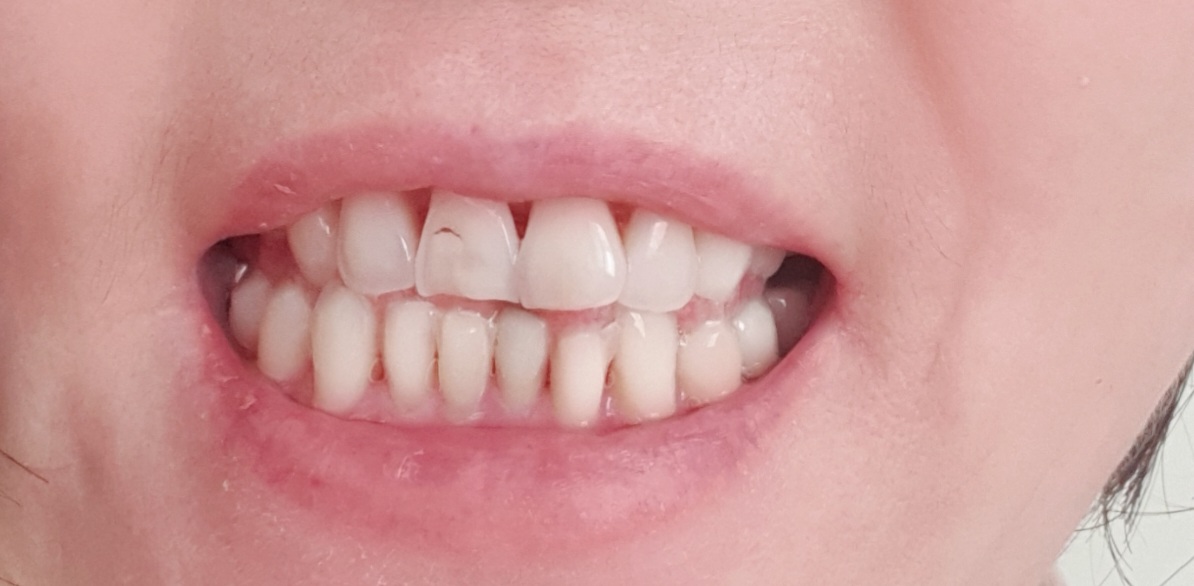

전

후

거리가 멀어서 고민을 많이했습니다 몸도 고생하고 돈도 많이들어가서 걱정했는데 집앞에 다니는 치과와비교하니 가격적인면에서 너무도 비교되어 서울로 정하고 다니기로 맘먹은게 대만족을 느낍니다. 예뻐지는 치아모습에 자신감이 생깁니다